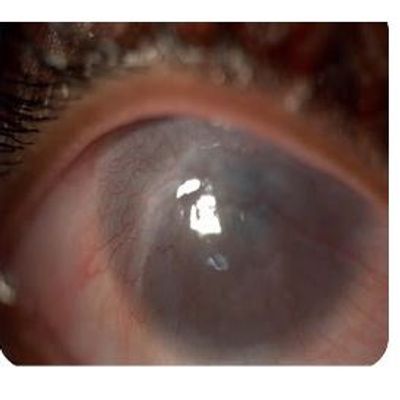

Culture of retinal pigment epithelium cells on the Mimetix scaffold. The aim of this case study was to evaluate whether the Mimetix scaffold can mimic Bruch’s membrane and assess the attachment, proliferation and differentiation of human RPE cells (ARPE-19) cells within it as a treatment option for age-related macular degeneration. Age-related macular degeneration (AMD) is the most common cause of blindness in the UK, causing vision loss as a result of permanent damage or death to the retinal pigment epithelium (RPE) or photoreceptor cells in the retina. The ability to replace and regenerate RPE cells on Bruch’s membrane could possibly lead to a number of therapeutic options to treat the cellular loss and dysfunction typical of AMD and other progressive retinopathies.